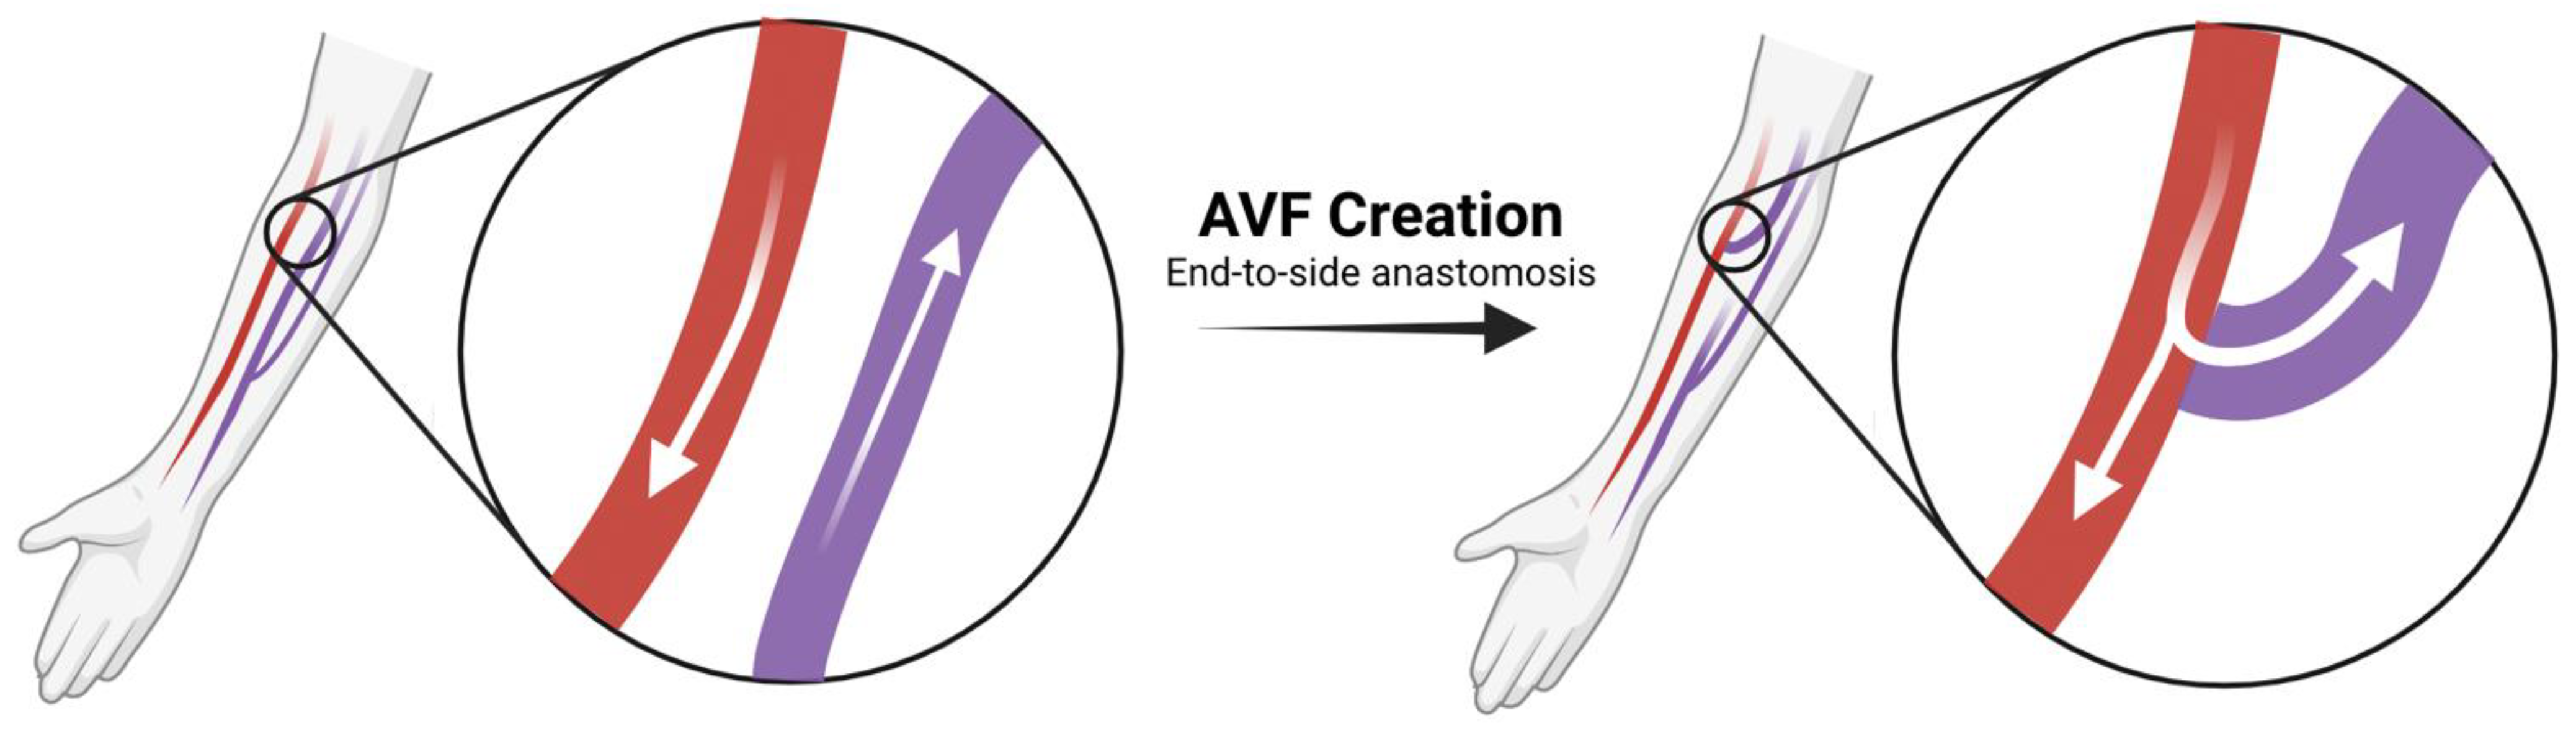

2. Pathophysiology of Venous Neointimal Hyperplasia

2.1. AVF Creation and the Physiology of Maturation